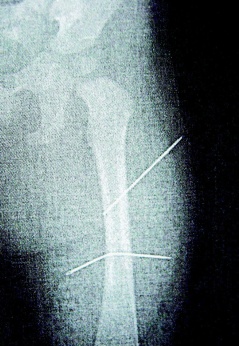

判決書指出,該女子去年照顧年僅9個(gè)月大外甥女,因外甥女哭鬧不停,情緒失控下拿家中縫衣針兩根,連刺入女娃左大腿內(nèi)側(cè),完全沒入皮下組織。

隔月27日,該女子又見外甥女哭鬧不停,拿蒼蠅拍朝著外甥女背部連打數(shù)十下,造成女娃背部瘀傷。經(jīng)女娃母親發(fā)現(xiàn)后送醫(yī)救護(hù),院方為女童進(jìn)行X光片照射后,才發(fā)現(xiàn)女娃左大腿里竟有兩根縫衣針。